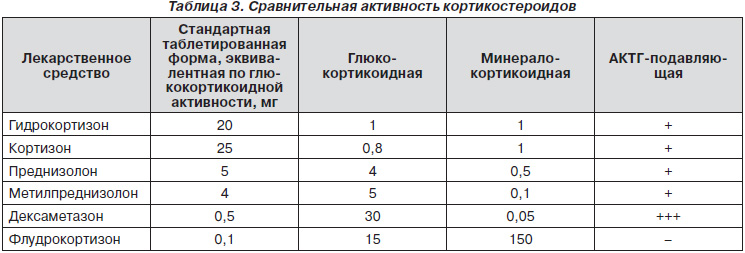

В системе «гипоталамус — гипофиз — надпочечники» действует классический принцип «отрицательной обратной связи», в соответствии с которым ГКС подавляют образование кортикотропин-рилизинг-гормона и адренокортикотропного гормона. ГКС обладают различной АКТГ-подавляющей активностью.

В отличие от ГКС-рецепторов, распространенных по всему организму, альдостероновые рецепторы сосредоточены преимущественно в области дистальных извитых канальцев нефрона. ГКС обладают высоким аффинитетом не только к собственным, но и к альдостероновым рецепторам. Однако фермент 11а-гидроксистероиддегидрогеназа, присутствующий в почках, превращает кортизол в биологически малоактивный кортизон. Из всех кортикостероидов только альдостерон и флудрокортизон не подвергаются инактивации, что обусловливает их высокую минералокортикоидную активность. Интересно, что флудрокортизон обладает в 200–400 раз большей минералокортикоидной активностью, чем кортизол, хотя отличается от последнего всего одним атомом фтора. Именно этот атом фтора защищает флудрокортизон от действия 11а-гидроксистероиддегидро-геназы и позволяет тому стимулировать альдостероновые рецепторы (табл. 3).